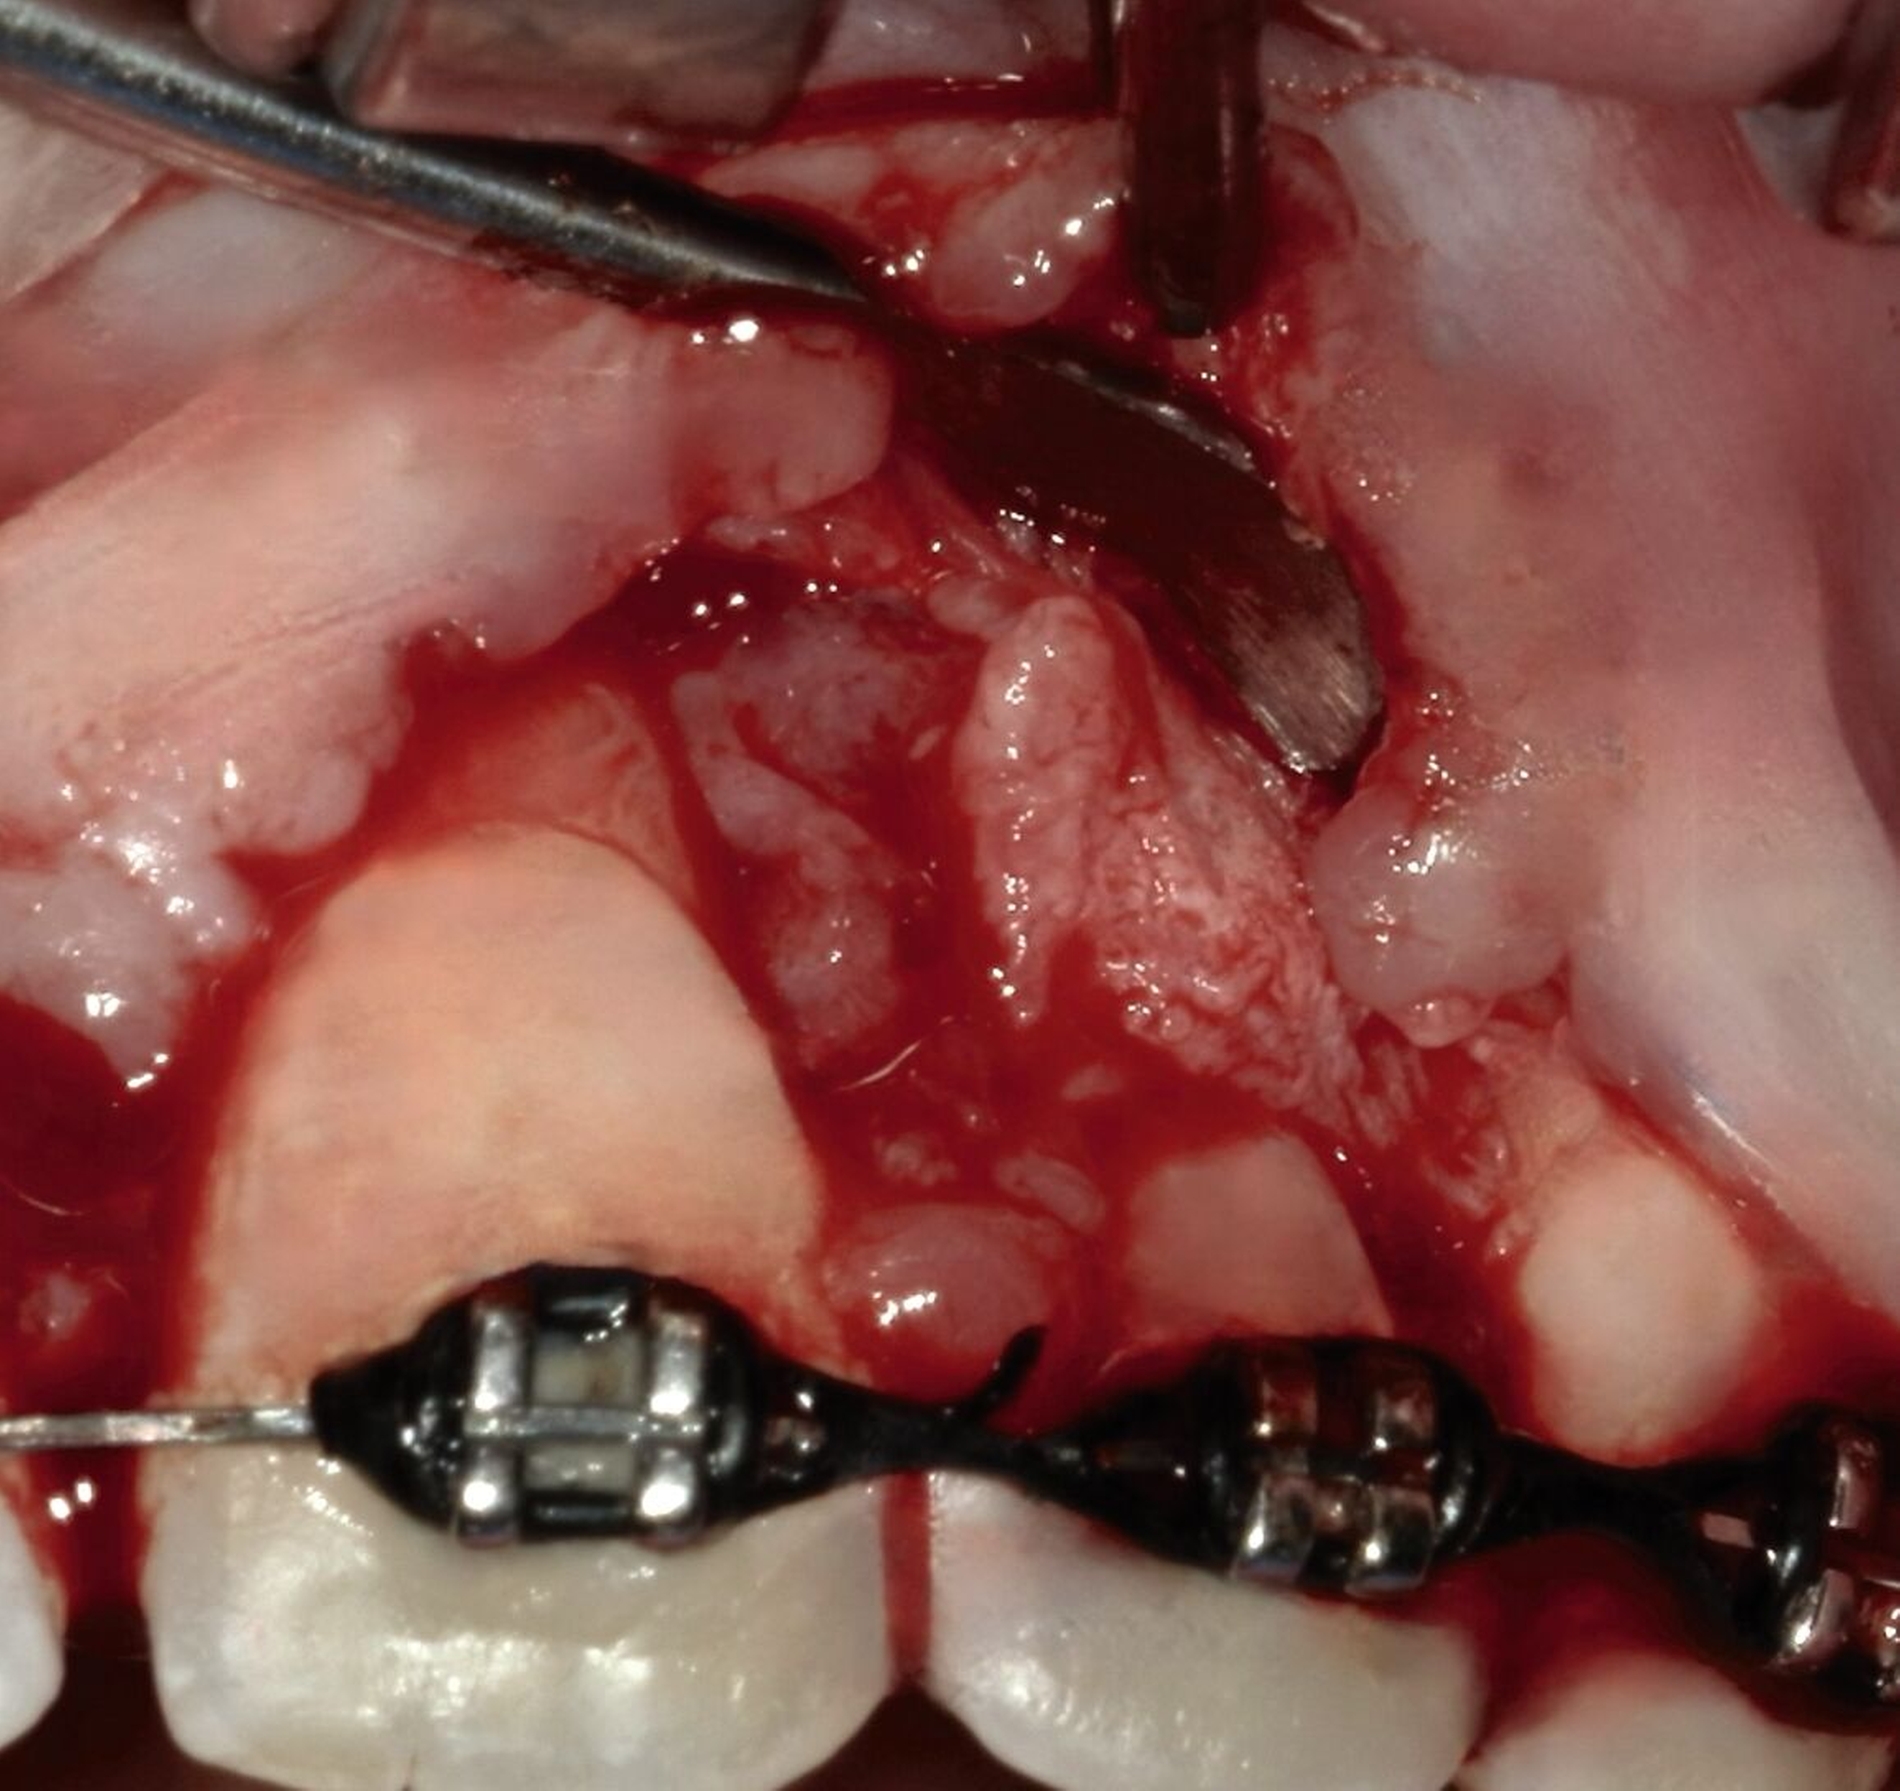

Die Pulpenvitalität der angrenzenden Zähne 21 und 22 war erhalten. Basierend auf der Anamnese, dem klinischen Befund und dem radiologischen Bild wurde die Verdachtsdiagnose eines benignen odontogenen Tumors gestellt. Als Therapie der Wahl erfolgte die Enukleation des Befundes in toto unter Lokalanästhesie. Nach Mobilisation des Mukoperiostlappens wurde ein Weichgewebssack sichtbar. Die Tumorkapsel war fest am intraalveolären Knochen fixiert (Abbildung 3).

Die entstandene ossäre Kavität wurde mit einem Knochenersatzmaterial mit Kollagenzusatz aufgefüllt, und es wurde ein plastischer Wundverschluss durchgeführt (Abbildung 4). Das entnommene Gewebe wurde zur histopathologischen Untersuchung in die Pathologie der Universitätsmedizin Mainz eingesandt. Histologisch zeigte sich ein zellarmes, bindegewebiges Stroma mit strangförmig angeordneten Zellen odontogenen Epithels.